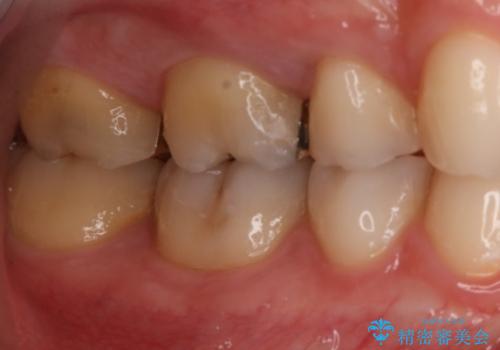

- 右上大臼歯の再治療を希望され来院された患者様です。

切削量と形状を考慮し、インレーでの治療を計画しました。

患者様がゴールドを希望されたのでゴールドインレーを選択しました。